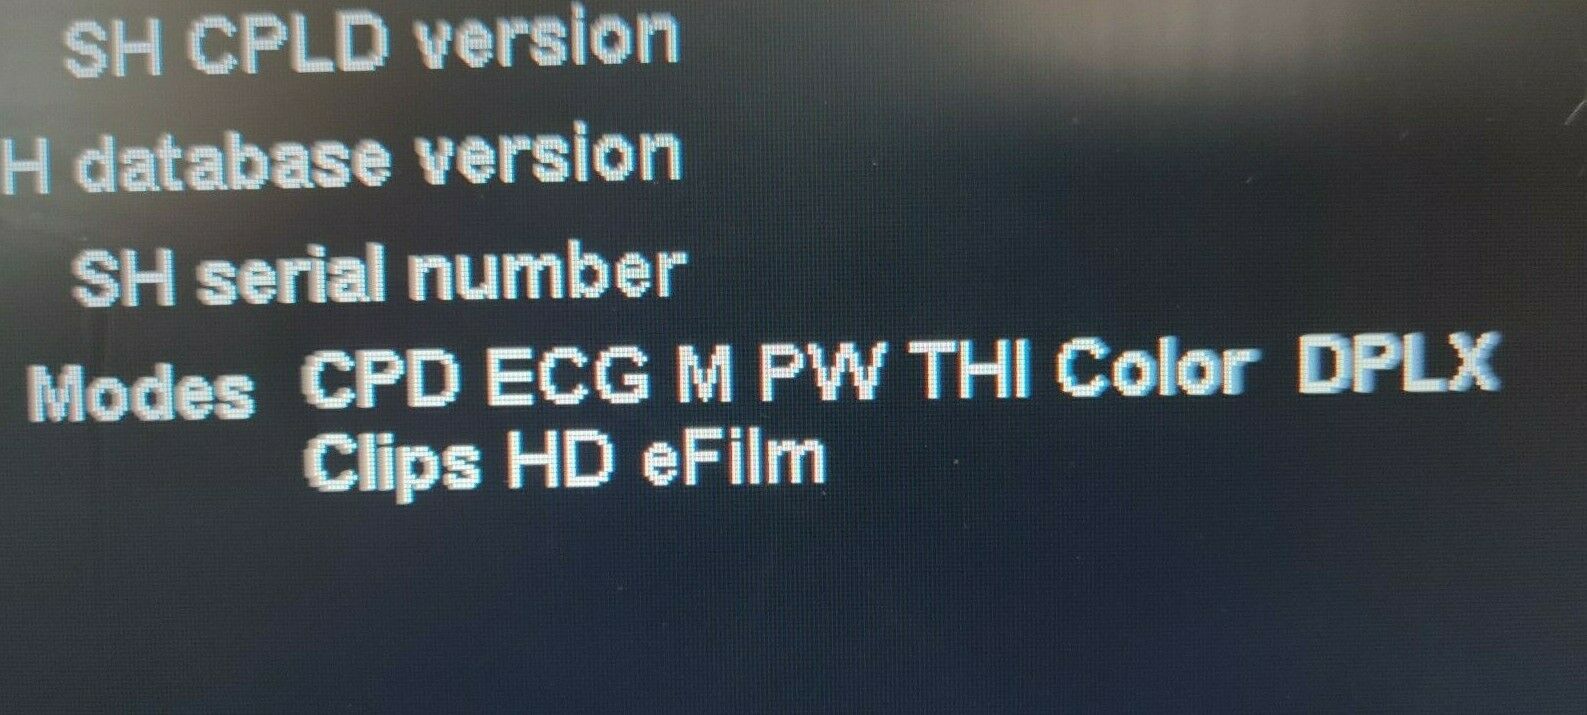

The Sonosite M-Turbo Portable is compatible with a wide range of probes and transducers, enhancing its versatility across various medical disciplines. Whether it's for abdominal imaging, vascular assessments, or musculoskeletal evaluations, this ultrasound machine delivers precise and dependable images. Moreover, the device supports advanced imaging modes such as Color Doppler, M-Mode, and Power Doppler, providing comprehensive diagnostic options for practitioners.

Another key aspect of the Sonosite M-Turbo Portable is its integration capabilities. The machine can easily connect to hospital networks and electronic medical records (EMRs), facilitating seamless data transfer and ensuring that patient information is readily available to healthcare teams. This connectivity feature streamlines workflow and enhances collaboration among medical professionals.